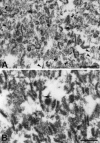

Transient ischemia leads to changes in synaptic efficacy and results in selective neuronal damage during the postischemic phase, although the mechanisms are not fully understood. The protein composition and ultrastructure of postsynaptic densities (PSDs) were studied by using a rat transient ischemic model. We found that a brief ischemic episode induced a marked accumulation in PSDs of the protein assembly ATPases, N-ethylmaleimide-sensitive fusion protein, and heat-shock cognate protein-70 as well as the BDNF receptor (trkB) and protein kinases, as determined by protein microsequencing. The changes in PSD composition were accompanied by a 2.5-fold increase in the yield of PSD protein relative to controls. Biochemical modification of PSDs correlated well with an increase in PSD thickness observed in vivo by electron microscopy. We conclude that a brief ischemic episode modifies the molecular composition and ultrastructure of synapses by assembly of proteins to the postsynaptic density, which may underlie observed changes in synaptic function and selective neuronal damage.